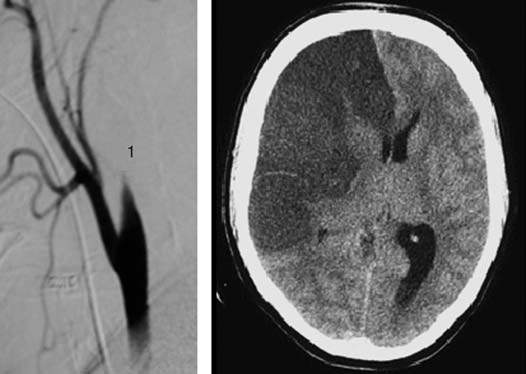

Dissection traumatique de la carotide interne droite avec une ischémie du territoire carotidien

Figure 3. Dissection traumatique de la carotide interne droite avec une ischémie du territoire carotidien. 1. Carotide interne.